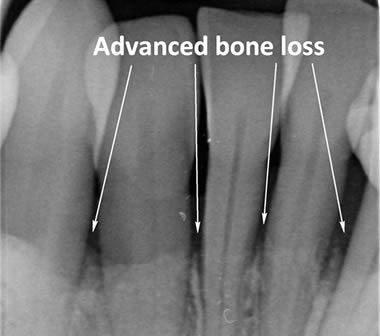

The diagrams below show the different stages of gum disease

Periodontitis is a more advanced stage of gum disease where there has been damage to the bone which supports the teeth. If left untreated periodontitis leads to more and more bone loss until the teeth start to become loose and eventually fall out by themselves or need to be extracted by a Dentist.

The main cause of gum disease is plaque. Plaque consists of millions of bacteria which live on and around the teeth and gums. These bacteria produce toxins which damage the gums. To begin with the gums start to peel away from the teeth and “pockets” form. As the bacteria penetrate deeper into these “pockets” they then start to cause damage to the bone which holds the teeth in. As more bone loss occurs the teeth start to become increasingly looser until they eventually start to fall out one by one.

In cases of advanced gum disease our Hygienist’s will also carry out deep scaling which cleans the root surfaces beneath the gum level. When pockets develop in the gums around the teeth plaque bacteria and calculus form on the root surfaces of the teeth and are protected from toothbrushing by the overlying gum. However, our Hygienist’s have special thin scaling instruments which can go down inside the pockets to clean the root surfaces. This treatment is carried out in small sections under local anaesthetic to ensure that you are comfortable throughout the treatment.